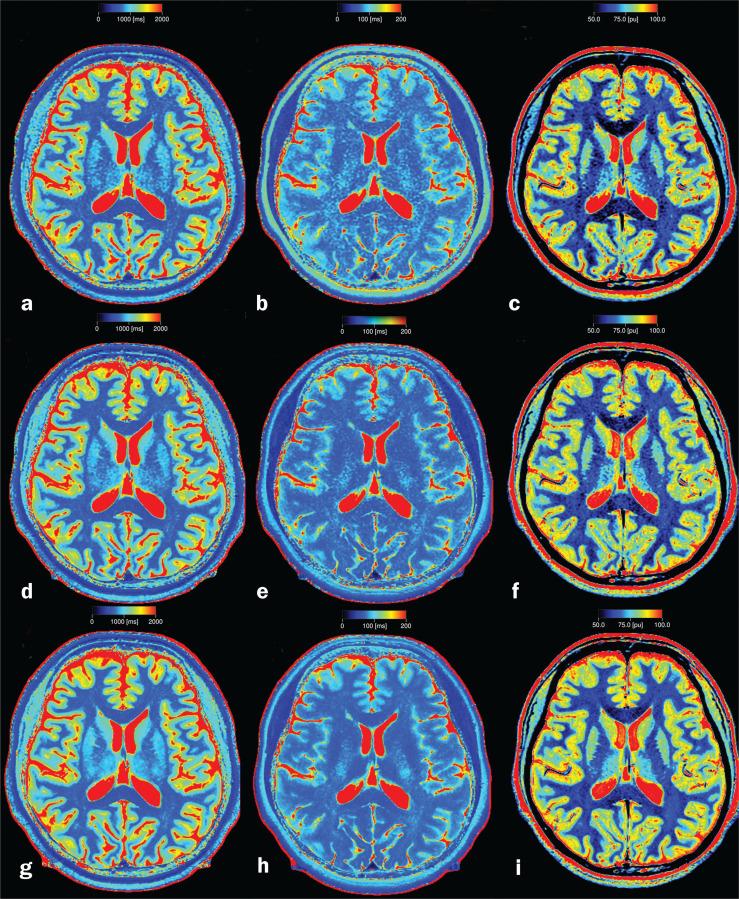

Synthetic MRI is being increasingly used for the quantification of brain longitudinal relaxation time (T1), transverse relaxation time (T2), and proton density (PD) values. However, the effect of fast imaging protocols on these quantitative values has not been fully estimated. The purpose of this study was to investigate the effect of fast scan parameters on T1, T2, and PD measured with a multi-dynamic multi-echo (MDME) sequence of normal brain at 3.0T. Thirty-four volunteers were scanned using 3 MDME sequences with different scan times (named Fast, 2 min, 29 sec; Routine, 4 min, 07 sec; and Research, 7 min, 46 sec, respectively). The measured T1, T2, and PD in 18 volumes of interest (VOI) of brain were compared between the 3 sequences using rank sum test, t test, coefficients of variation (CVs) analysis, correlation analysis, and Bland-Altman analysis. We found that even though T1, T2, and PD were significantly different between the 3 sequences in most of the brain regions, the intersequence CVs were relatively low and linear correlation were high. Bland-Altman plots showed that most of the values fall within the 95% prediction limits. We concluded that fast imaging protocols of MDME sequence used in our study can potentially be used for quantitative evaluation of brain tissues. Since changing scan parameters can affect the measured T1, T2, and PD values, it is necessary to use consistent scan parameter for comparing or following up cases quantitatively.

合成磁共振成像(MRI)正越来越多地用于量化脑纵向弛豫时间(T1)、横向弛豫时间(T2)和质子密度(PD)值。然而,快速成像协议对这些定量值的影响尚未得到充分评估。本研究的目的是探讨快速扫描参数对在3.0T下使用多动态多回波(MDME)序列测量的正常脑T1、T2和PD的影响。34名志愿者使用3种不同扫描时间的MDME序列进行扫描(分别命名为快速序列,2分29秒;常规序列,4分07秒;研究序列,7分46秒)。使用秩和检验、t检验、变异系数(CVs)分析、相关性分析和Bland-Altman分析比较了3种序列之间在18个脑感兴趣区(VOI)中测量的T1、T2和PD。我们发现,尽管在大多数脑区3种序列之间的T1、T2和PD存在显著差异,但序列间的CVs相对较低且线性相关性较高。Bland-Altman图显示,大多数值落在95%预测限内。我们得出结论,我们研究中使用的MDME序列快速成像协议有可能用于脑组织的定量评估。由于改变扫描参数会影响测量的T1、T2和PD值,因此在定量比较或随访病例时,有必要使用一致的扫描参数。